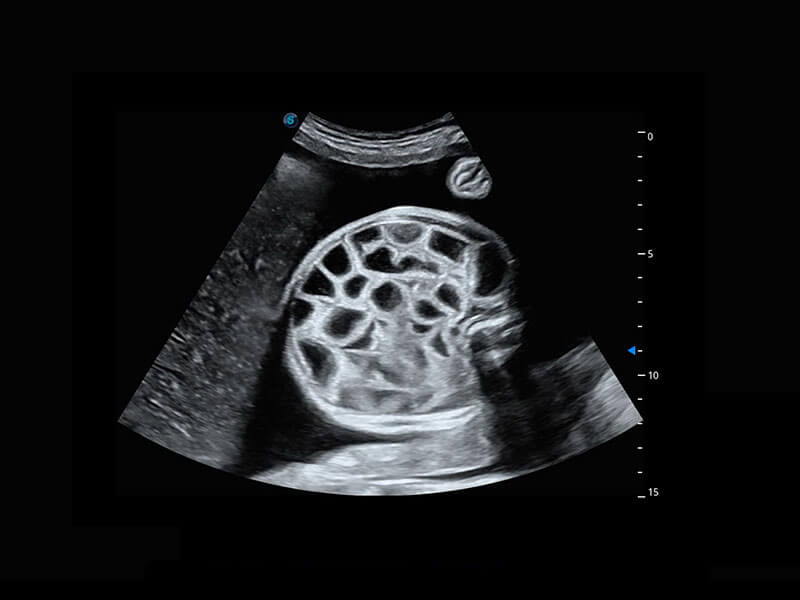

生殖健康

P60优异的图像质量搭载专科探头,在妇科基础疾病的诊断、卵泡生长的监测、输卵管通畅情况的判别等方面为您提供生殖应用方案。

• 腔内妇科-卵巢

• 腔内三维-宫内节育器

• 腔内三维-光影成像